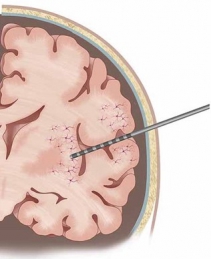

Our research leverages on the rare opportunity of measuring brain activity intracranially in patients affected by pharmaco-resistant epilepsy. In pharmaco-resistant epilepsy patients, neurologists use intracranial electroencephalography (iEEG) to delineate the epileptogenic focus, when non-invasive scalp EEG and other techniques have been insufficient to localize it. iEEG is recorded with intracranial electrodes and it has higher spatial resolution and higher signal-to-noise ratio than scalp EEG.

In addition to the very valuable iEEG recordings from the clinical macroelectrodes, our iEEG recordings also include signals recorded with microelectrodes. The additional microelectrodes have a diameter of about 40 μm (smaller than the hair) and spread out of the tip of the clinical intracranial electrode. They are added solely for research purposes and, because of their small size, they can record the electrophysiological firing activity generated by nearby individual neurons. We analyze this data by using algorithms which classify the different waveforms recorded by a single microwire into action potentials generated by different neurons. We also use population decoding methods to extract the information associated by the neurons (e.g. “concept” neurons which preferably fire in response to specific images of the same individual). To localize the site of the macro- and micro-electrodes with high spatial resolution, we combine post-implantation CT scans with pre-implantation neuroimaging scans from the 7-Tesla MRI, available at the University of Magdeburg.

1. © Grande et al. 2020. The image is a cropped version of the original. Reproduced according to the terms of Creative Commons Attribution License. Grande, Krista M., Sarah K. Z. Ihnen, and Ravindra Arya. 2020. “Electrical Stimulation Mapping of Brain Function: A Comparison of Subdural Electrodes and Stereo-EEG.” Frontiers in Human Neuroscience 14 (December). https://doi.org/10.3389/fnhum.2020.611291.

2. © Greene et al., 2021. Reproduced according to the terms of Creative Commons Attribution License. Greene, Patrick, Adam Li, Jorge González-Martínez, and Sridevi V. Sarma. 2021. “Classification of Stereo-EEG Contacts in White Matter vs. Gray Matter Using Recorded Activity.” Frontiers in Neurology 11 (January). https://doi.org/10.3389/fneur.2020.605696.